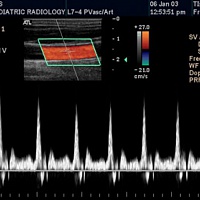

Доплерография – это исследование и диагностика состояния кровеносных сосудов при помощи ультразвуковых волн. Одним из главных преимуществ доплерографии является её наглядность. Используя в своей работе аппарат Philips Clear Vue, наши специалисты получают двухмерное цветное изображение, на основе которого делается вывод о наличии или отсутствии каких-либо затруднений кровотока, проблем сосудистой системы, венозных заболеваний.

- скорость тока крови;

- ширину сосудов;

- наличие и величину закупорки сосуда;